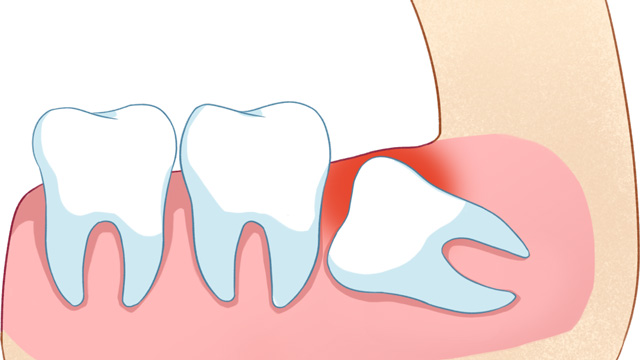

01智齿挤压邻牙,导致牙齿拥挤/移位

这是最常见的拔除原因。正畸的核心需求之一一般是“排齐拥挤牙齿”,而智齿作为口腔中最后萌出的牙齿(通常在20岁左右萌出),由于生长位置特殊、空间有限,很可能会持续挤压旁边的第二磨牙,导致第二磨牙倾斜、移位,进而引发整个牙列拥挤。

如果不拔除这颗“肇事智齿”,即使通过正畸排齐了牙齿,后期也会因为智齿的持续挤压,导致牙齿再次拥挤、反弹。